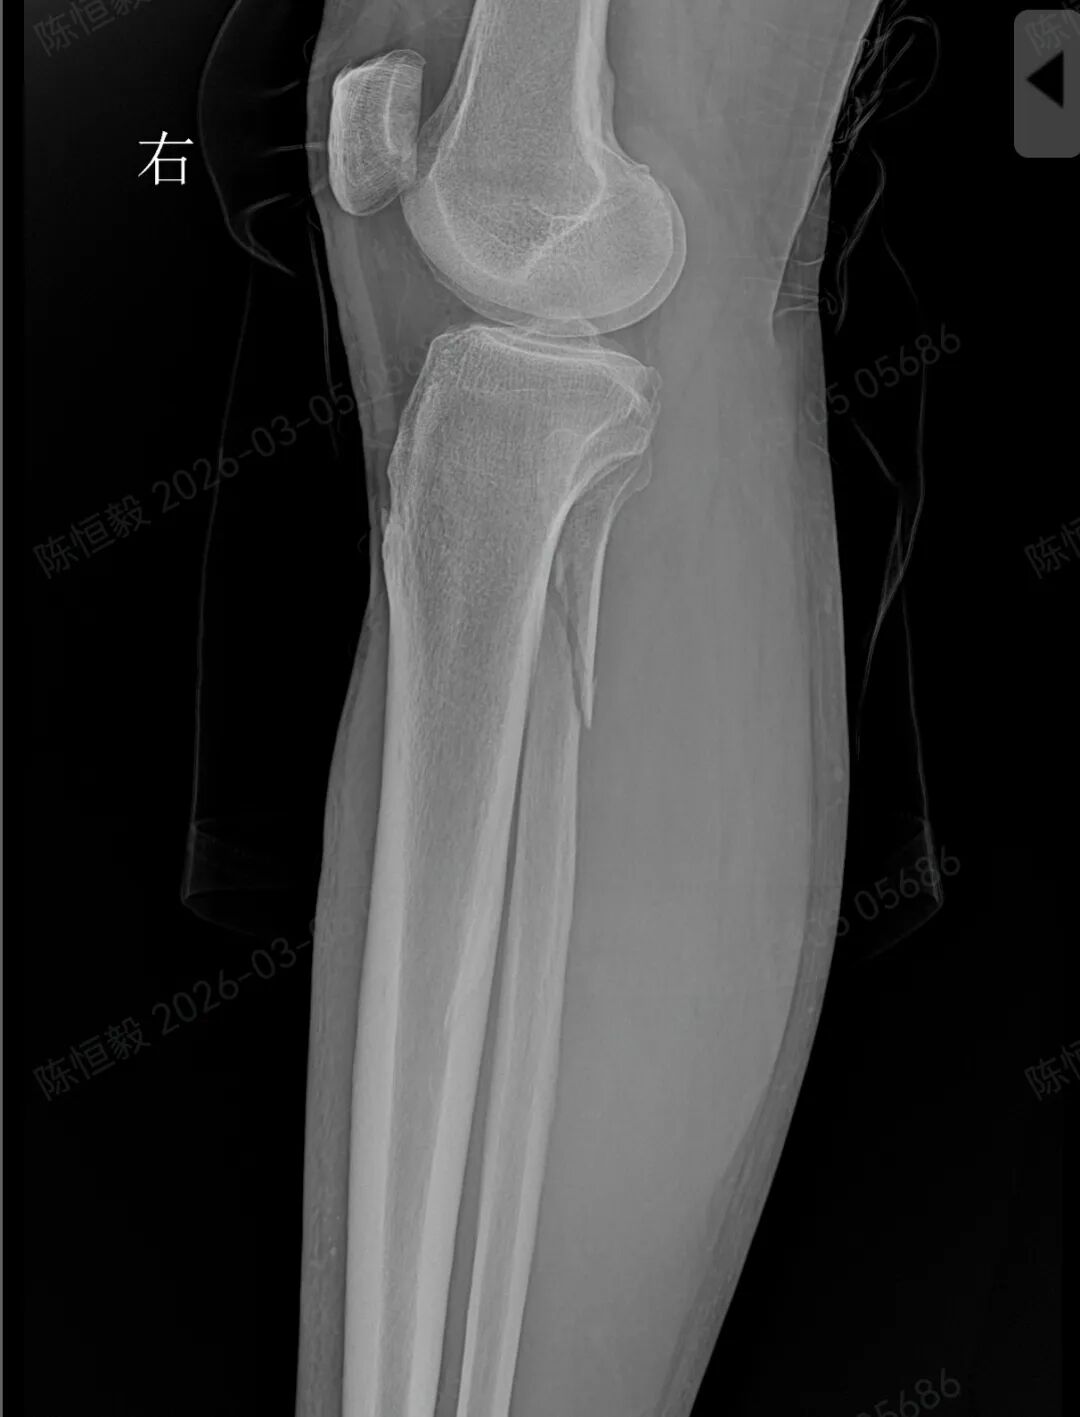

王大爷听从建议住院后,经完善体格检查及 CT 检查,最终确诊为复杂的 Maisonneuve 骨折:不仅存在下胫腓分离,还合并前踝 Chapute 结节撕脱骨折、后踝骨折、内踝骨折,同时伴有腓骨高位骨折。

普通 X 光片仅能判断是否存在明显骨折、脱位,对于下胫腓联合损伤、微小骨折、软骨损伤,以及 Maisonneuve 骨折涉及的腓骨高位骨折等隐匿性损伤,很难清晰显示。